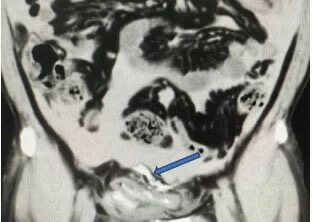

箭头处可见外渗进腹腔的造影剂 膀胱为何会“破”? 该医院泌尿外科李晟主任分析这是一个“连环效应”。一是外力撞击腹部受击时,因未戴护具,膀胱壁可能已受损。二是饮酒+憋尿随后大量饮酒,导致膀胱感觉变得迟钝,更容易长时间憋尿,使膀胱内压力持续升高。 三是膀胱破裂在原有损伤的基础上,内压超过极限,导致膀胱破裂。“必须立即手术,否则尿液持续渗入腹腔,会导致感染性腹膜炎、脓毒症,危及生命。”李主任强调。 取得患者及家属同意后,张先生被紧急送入手术室,行腹腔镜下膀胱破裂修补术。 术中发现其膀胱顶部有一长约5厘米的破口,腹腔内积存约1500毫升血性液体,肠道已被从膀胱流出的尿液浸泡。医疗团队迅速完成修补,手术顺利进行。 {jz:field.toptypename/}术后张先生恢复良好,次日即可排气排便,尿液引流正常。通过微创手术治疗,其腹壁仅留三个0.5-1cm的微小创口。经过一周住院治疗,术口已拆线,创口愈合良好,现已康复出院。 李晟副主任医师特别提醒: 下腹部遭受外力撞击后,如果伴有腹痛、排尿困难或血尿,应高度警惕膀胱损伤,立即就医。饮酒会降低膀胱敏感性,切忌长时间憋尿,否则极大增加破裂风险。 一旦确诊为外伤性膀胱破裂,绝大多数需要手术修补,同时探查有无其他脏器损伤,避免严重感染。运动或日常活动中,注意保护腹部,避免重击;饮酒后应及时排尿,切勿强忍。“记住身体异常,千万别硬扛,及时就医是关键。” 来源:广州日报 |